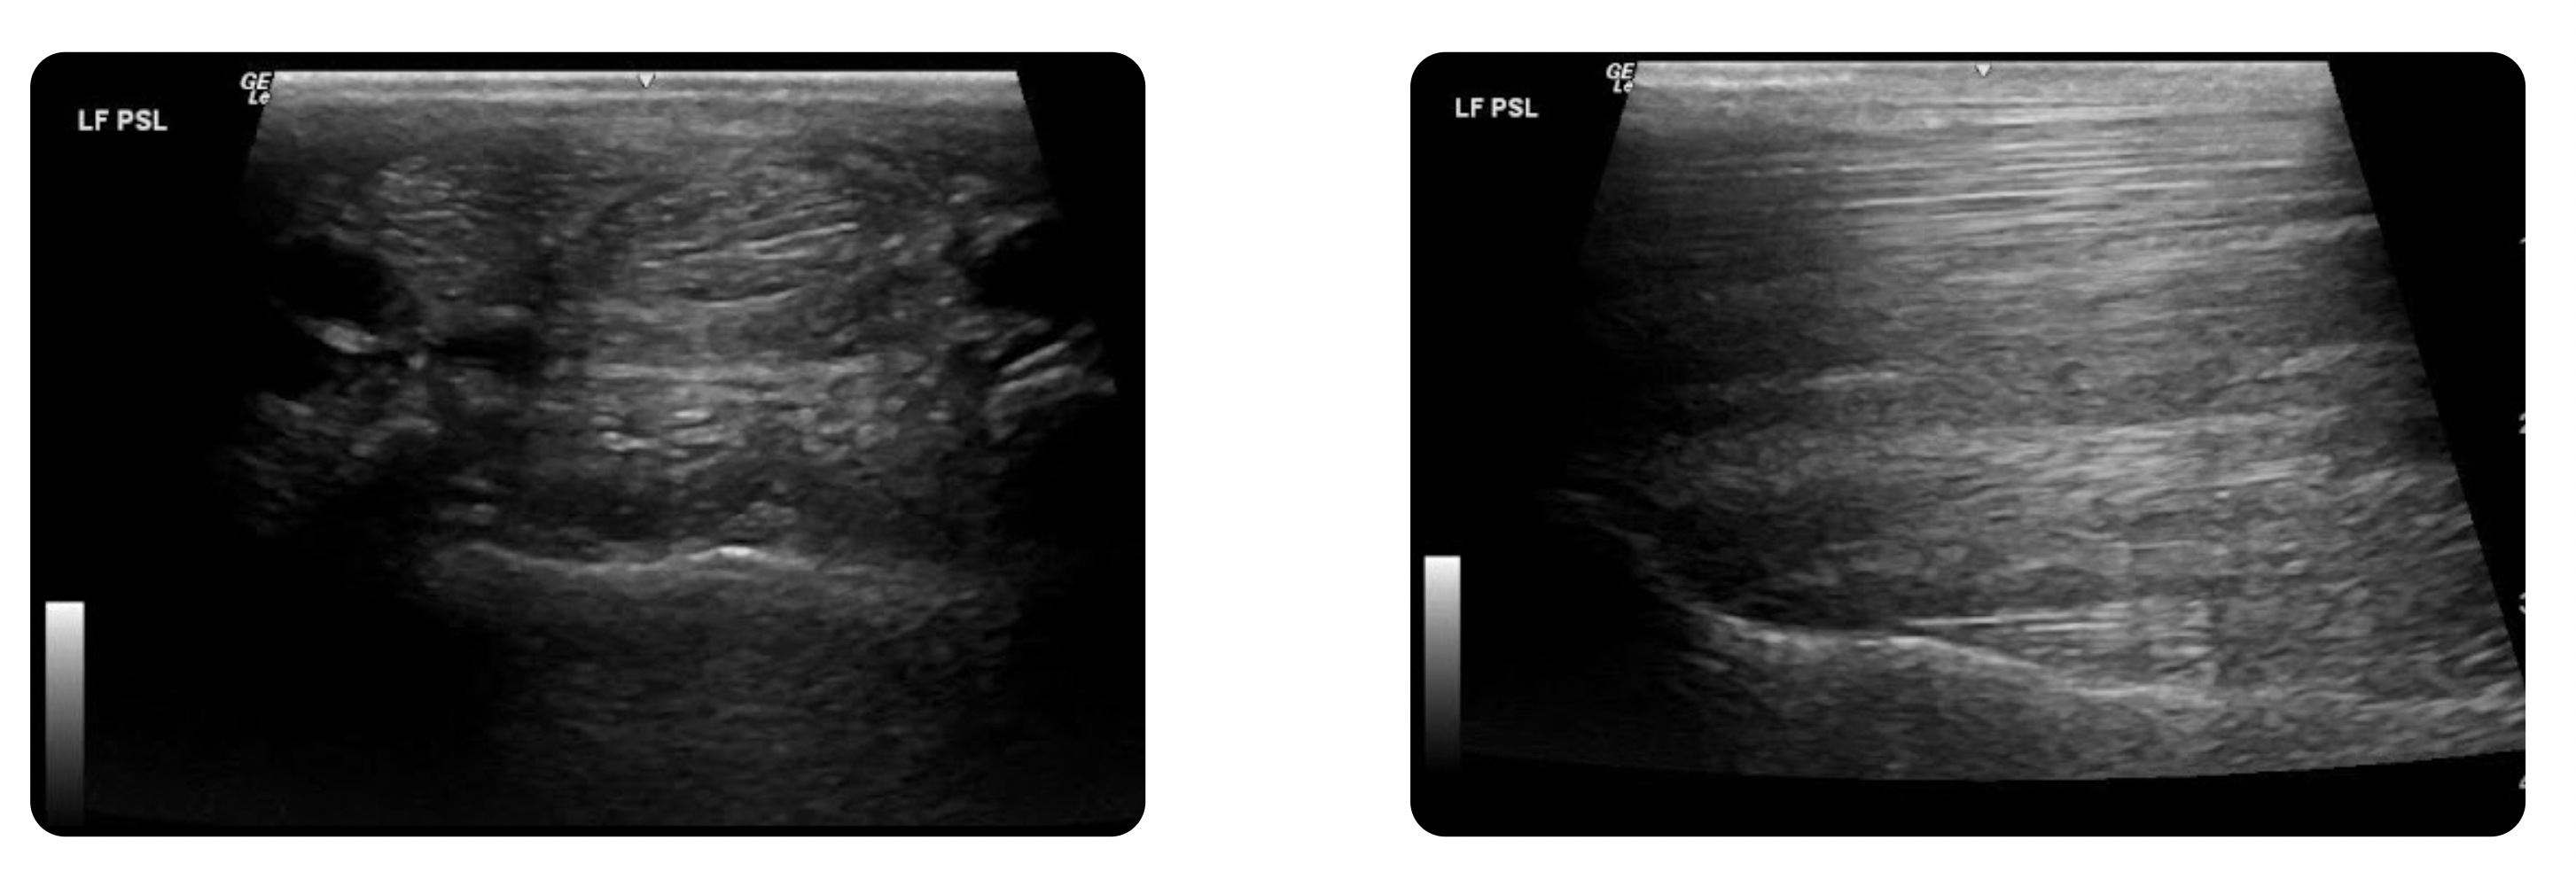

“At that point, we went to imaging, given the likelihood of bilateral proximal suspensory issues,” Dr Beau Whitaker explains.

Ultrasound revealed signs of chronic scar tissue and mixed echogenicity in both left and right front proximal suspensory ligaments. The findings were consistent with a chronic active proximal suspensory desmitis, indicating a wear-and-tear issue rather than an acute injury.

“If I hadn’t seen anything on the imaging, I would have gone back to blocking the right front limb”, says Dr Beau Whitaker.